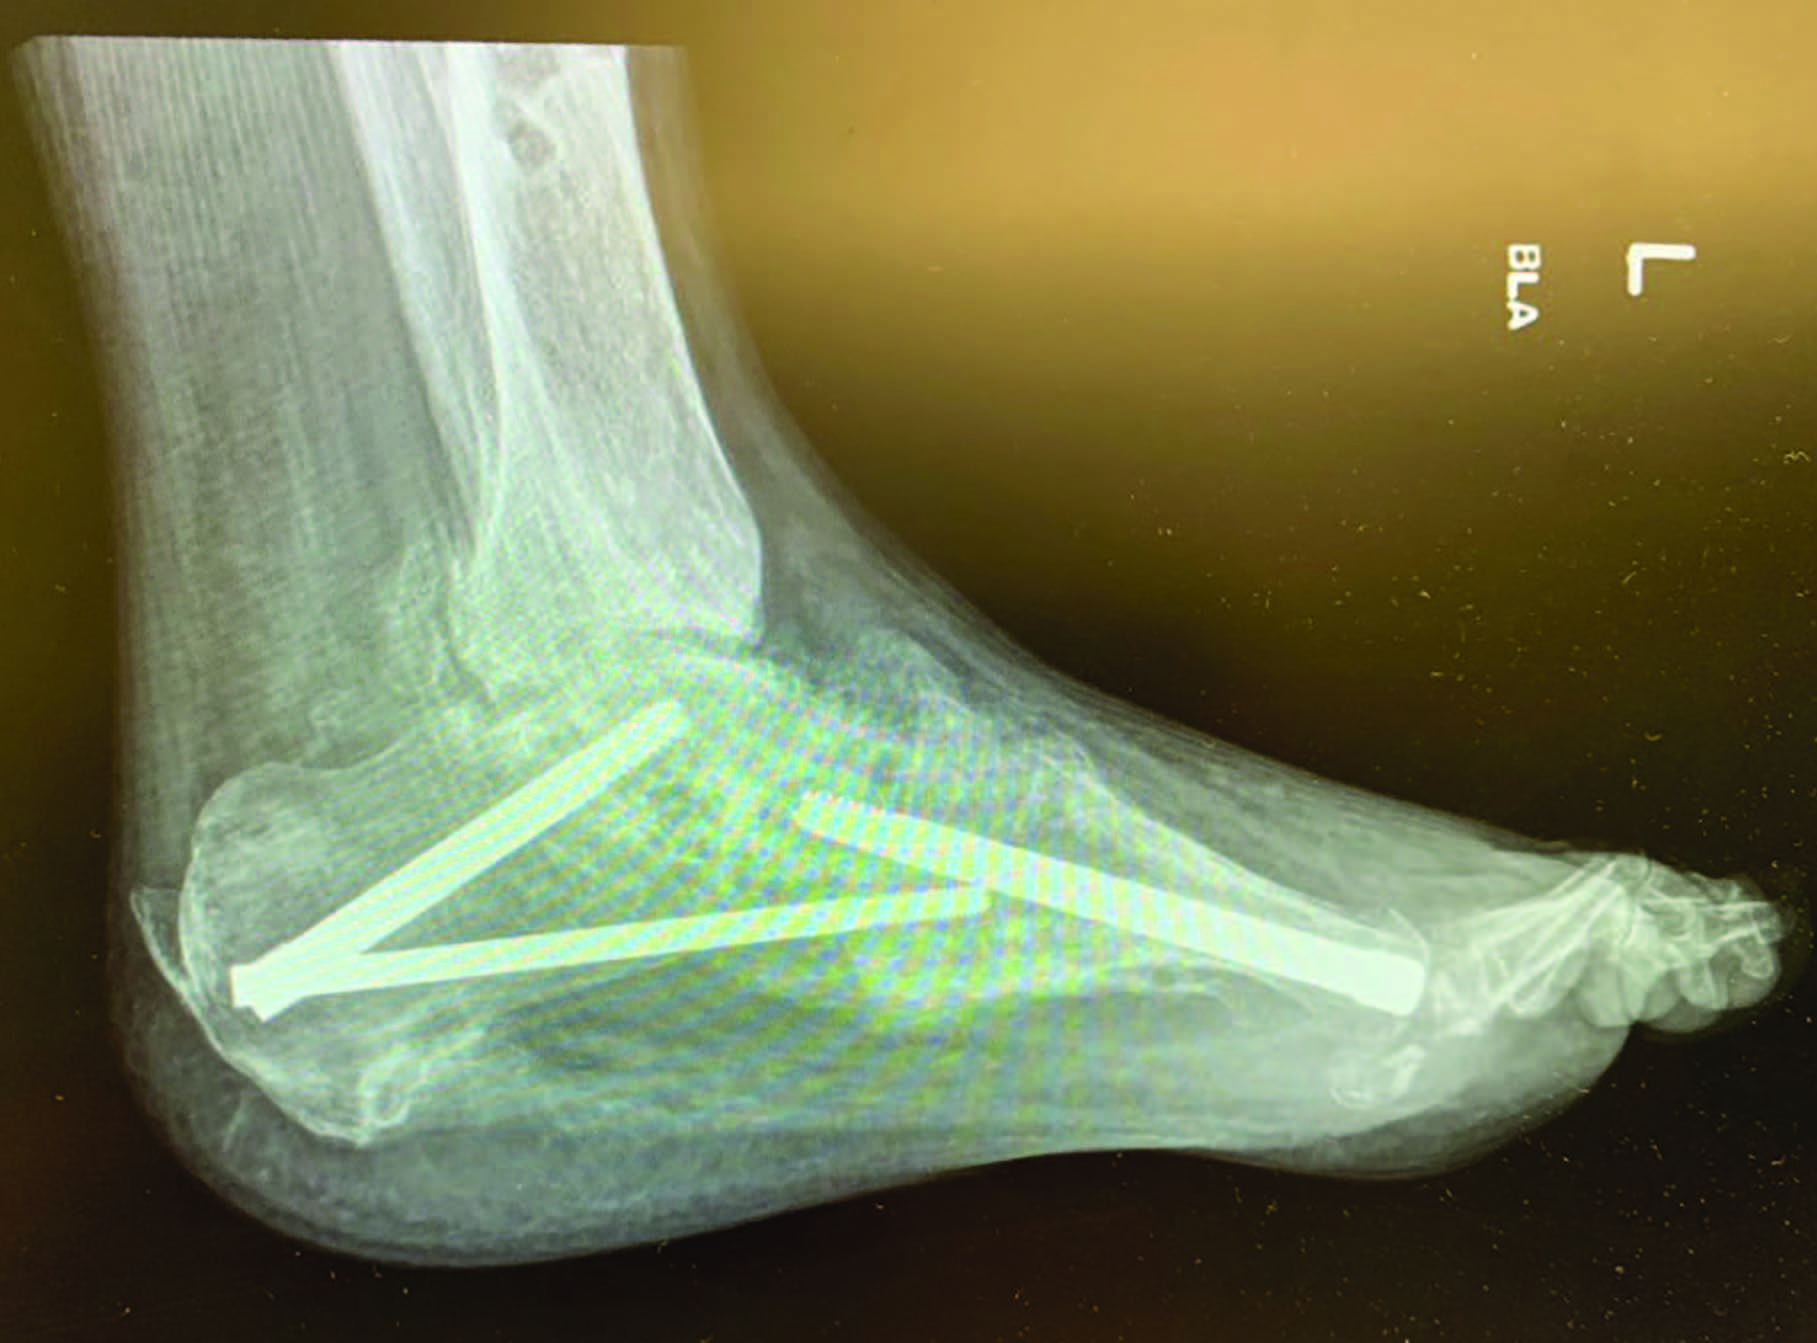

William P. Grant, DPM popularized the concept of beaming in Charcot,2 and subsequent modification and perfection continues through more recent literature.3 Beaming the medial column with large diameter screws was first mentioned at the American College of Foot and Ankle Surgeons conference in 1997.4 Since then, literature supports 2 to 3 beams in the medial and lateral columns, and the hindfoot for more stability.2 Beaming the midfoot and hindfoot acts like reinforcement rods, or rebar, to accept compressive and tensile loads and compensate for inadequacies of native structures.

Grant and colleagues looked at beaming of the medial column only versus medial and lateral with and without subtalar joint arthrodesis.2 They found that with medial column beaming alone, the mechanical advantages of the posterior tibial tendon increased, which led to increased plantar lateral pressure and collapse of the non-beamed lateral column. They also found that locking the subtalar joint (via either arthrodesis or arthroereisis) further stabilized transverse and frontal plane torsion.2 Other studies confirmed that this 3-beam construct seems to be the most stable, with less chance of a secondary collapse in the foot.3,5 Other advantages of beaming include no cortical stress on the bone (unlike plates/screws), allowing for fixation beyond the site of collapse, making it more stable, and no exposed hardware in the presence of dehiscence.3